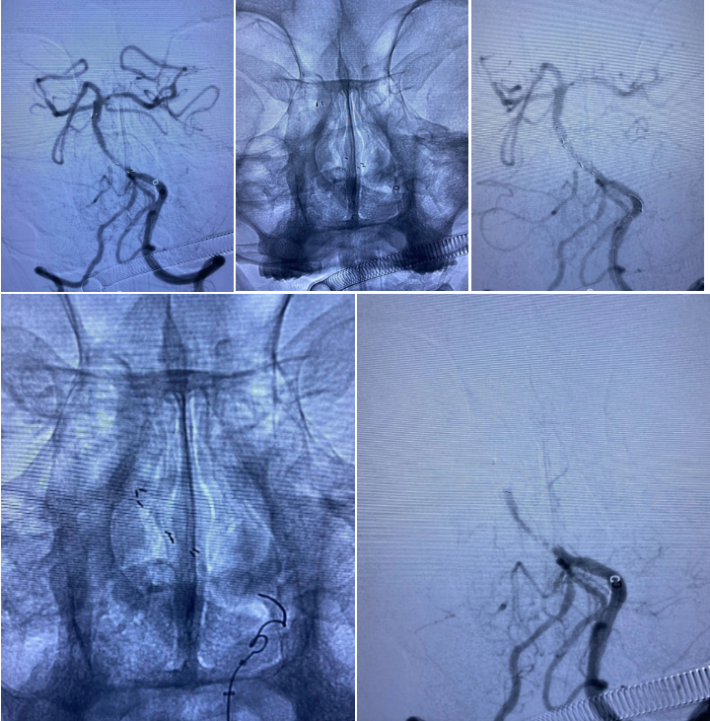

患者SCY,M59Y。2020年07月06日患者因症状性基底动脉重度狭窄,在外院行球囊扩张支架植入术。术中应用2.0mmx15mm Gateway球囊扩张,植入Enterprise 2 4.0mmx23mm支架,术后狭窄改善良好,患者无不适。规范应用双联抗血小板聚集治疗。

2020.07.10晚,患者术后第4天逐渐出现意识迷糊,嗜睡,考虑支架闭塞可能。遂急诊造影示:支架内血栓闭塞,意识模糊,危在旦夕,外院兄弟果断尝试再通,导丝导管通过后血流线样再通,撤回微导管注射替罗非班,血流难以维持。

再次尝试通过导丝导管,支架移位变形严重。

经过尝试,支架导管Rebar 18➕Synchro导丝200cm通过变形严重的原支架Enterprise 2。

打开取栓支架。

Solitaire AB 4mmx20mm成功挂住Enterprise 2。

尝试回收支架至5F Navien,牵扯力量比较大,提心吊胆。

经反复收拉尝试,最终取出Enterprise 2支架。

Enterprise 2支架在血管内两端严重变形,反折的Mark恰好被Solitaire AB支架咬合取出。

Enterprise 2支架经过体外揉搓,恢复了形态,支架内一同取出的还有一大坨增生的支架内血栓。

造影未见出血,血流良好,原狭窄在第一次支架时球囊扩张,现在狭窄已缓解。狭窄远端血管内膜稍不光滑。观察30min,血流稳定,为避免再放支架血栓,同时本次预后尚未知,暂不植入第二枚支撑支架,予以替罗非班注射液应用。